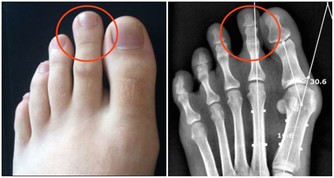

美國一名42歲的男子去非洲奈及利亞旅遊,當時他發現自己腳上的血管變得很清楚。

原本他以為只是類似靜脈曲張所以不在意,但一個月後,他發現這個血管竟然會在他腳步上下移動...

這名男子也以為自己有靜脈曲張的體質,過了一個月,

他發現這個痕跡越來越淡,但是位置卻跟以前差很多。

保險起見,他決定找了另一位醫生協助,才發現他腳上的紅色痕跡根本不是血管,是巨大的蠕蟲!